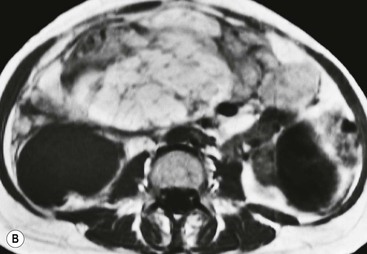

Hydatid disease is most commonly due to Echinococcus granulosus. Peritoneal hydatidosis is usually the result of traumatic or surgical rupture of hepatic hydatid disease and results in cystic, usually septated, thin-walled space-occupying lesions.12 CT is the method of choice in peritoneal seeding (Fig. 30-6). A calcifying rim is a suggestive feature. Ultrasound is useful for the detection of membranes, septa and hydatid sand within the cyst.